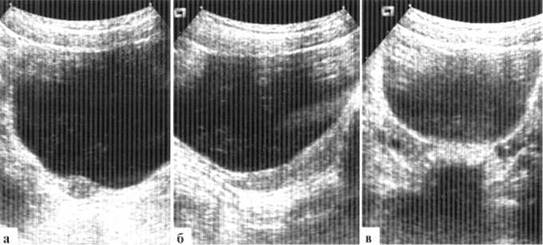

«Гипертрофированная» матка новорожденной в течении 1—3 месяцев подвергается инволюции, и в дальнейшем выглядит примерно одинаково как в 1 год, так и в 3, и в 6 лет. В этом возрасте суммарная длина матки с шейкой составляет около 3 см, ширина — около 1,5 см. Размеры матки у девочки только к 6—8 годам достигают размеров матки новорожденной (рис. 1.4). Постепенно изменяется и соотношение длины тела матки к шейке: к 4 годам оно достигает 1:1,7, к 7 годам 1:1,4, к 9 годам 1:1. Последняя цифра не точна: у некоторых девочек менархе наступает уже к 9 годам, внутренние гениталии уже имеют «взрослый» тип строения и это не считается патологией. Только к 8—9 годам начинает четко прослеживаться шеечно-маточный угол, который становится окончательно сформированным уже в пубертатном периоде. Примерно за полгода до наступления менархе матка начинает быстро увеличиваться в размерах, соотношение длины тела к шейке быстро достигает 2:1.

Размеры яичников у девочек нейтрального периода небольшие, составляют около 15x10 мм, могут дифференцироваться отдельные мелкие (до 3—4 мм) фолликулы. Довольно часто эхографически визуализировать яичники у девочек нейтрального периода не удается, и это не имеет самостоятельного клинического значения. К 7—8 годам в яичниках увеличивается количество фолликулов, размеры яичников достигают 20—25 мм в длину, 15 мм в ширину. Отдельные фолликулы могут достигать 7—10 мм в диаметре, число фолликулов может превышать 10 в каждом яичнике. Меняется топография яичников: они располагаются около углов матки.

Рис. 1.4. УЗИ внутренних гениталий у девочки 5 лет — «индифферентный тип»: а, б — поперечный и продольный сканы матки (двойная стрелка). Шеечно-маточный угол не выражен, толщина тела и шейки матки почти одинаковая, М-эхо не прослеживается; в — яичники (стрелки) содержат мелкие фолликулы, расположены высоко, визуализируются выше дна матки